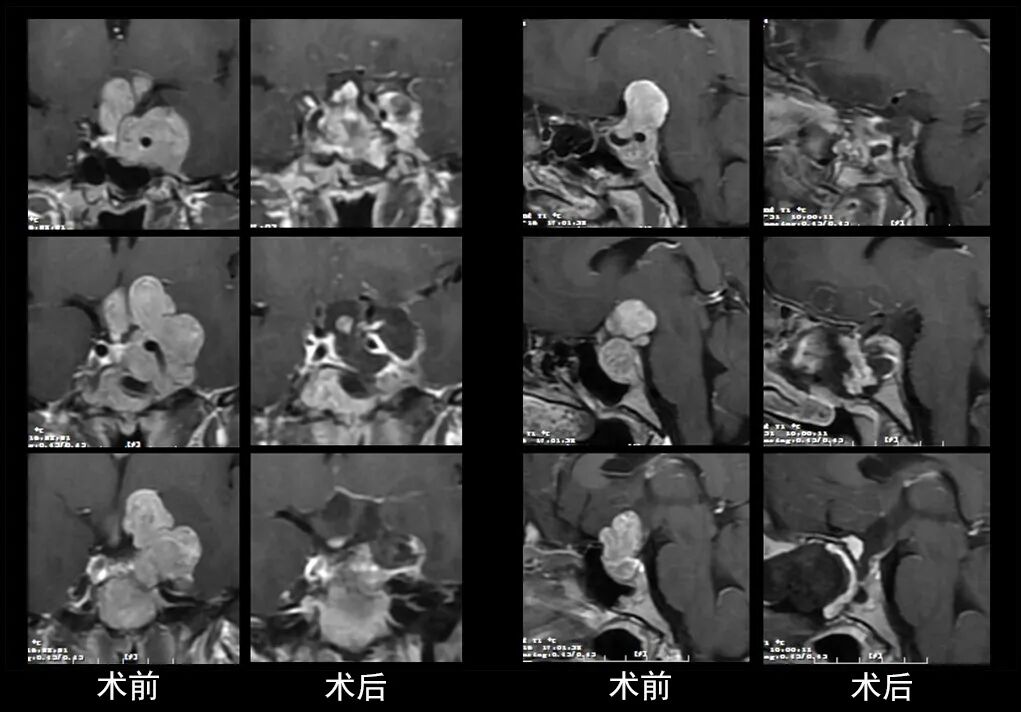

本研究中采用联合手术策略的代表性病例展示:

左右滑动查看更多

图片

case 1

case 2